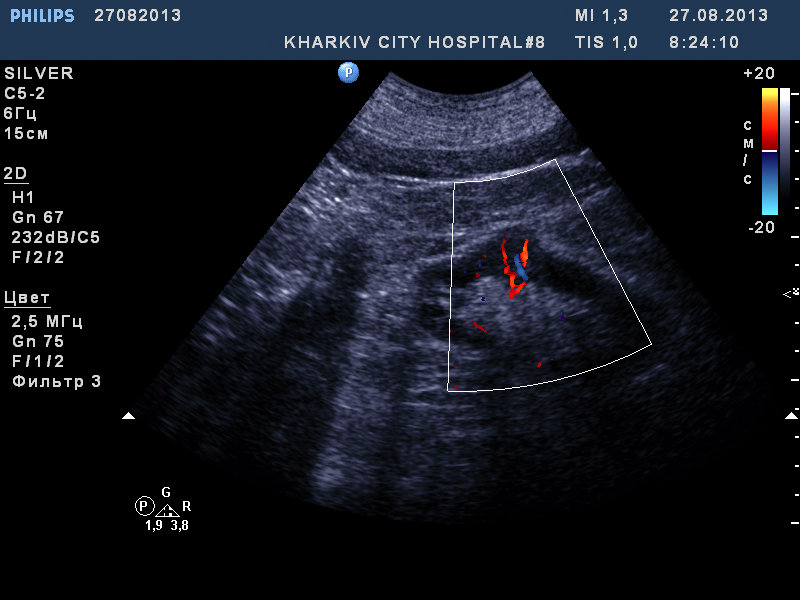

собственно такая картина.

если мой прицел не сбился, вероятно ПКР.

Рекомендовал КТ.

Хотелось бы видео продольного сканирования почки (как сонограммы 1 и 2) в полном объеме - от передней до задней поверхности.

Сосудистый рисунок сохранен на сонограммах 1 и 2.